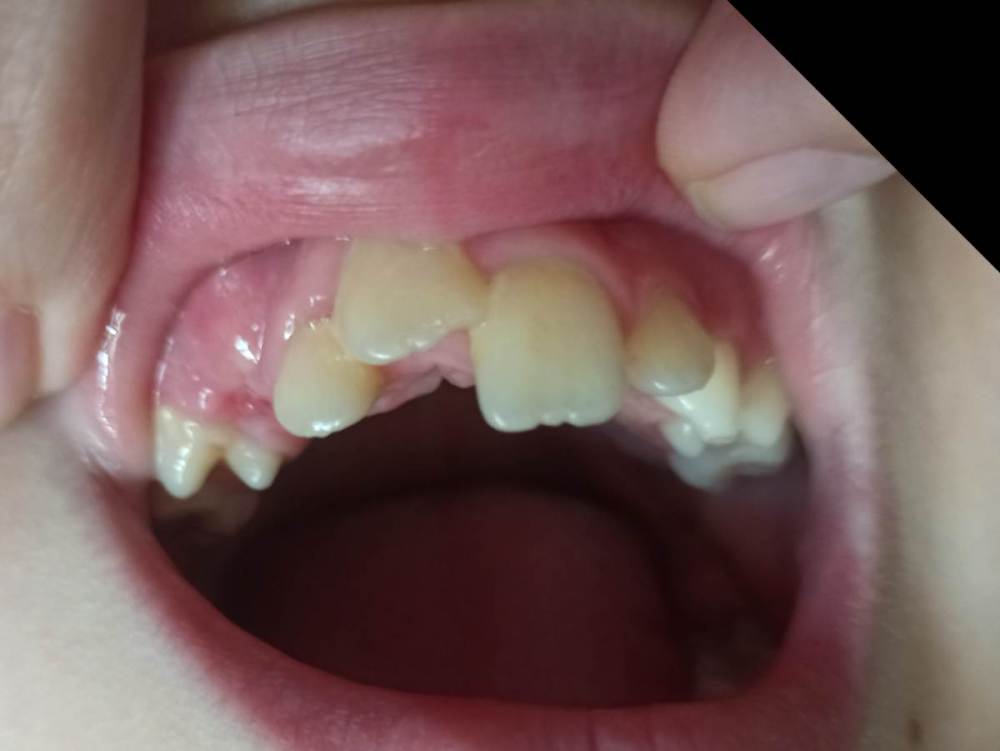

Pole4ka Опубликовано 4 июля, 2021 Поделиться Опубликовано 4 июля, 2021 Добрый день уважаемые специалисты. Три года назад у сына произошла травма, в возрасте 8 лет. Был выбит передний зуб, сломан альвеолярный участок кости. В нашем населённом пункте не было ни одного специалиста, который мог бы помочь в этой ситуации. Через три часа после травмы, были направлены в челюстно-лицевую хирургии в другом городе. Выбитый зуб находился в физрастворе. В итоге, была сделана операция, реплантирован зуб (верхушка зуба на тот момент была не сформирована), добавили костную ткань в месте перелома альвеолярной кости,наложили швы, поставили шины и вывели зуб из прикуса. В течение месяца наблюдались каждый день. Соблюдали все рекомендации по питанию и санации полости. В итоге, зуб прижился. Зуб не депульпировали! На сейчас он ничем не отличается от соседних, единственное, ушел вверх. Через год после травмы поставили расширительные пластины. Т. к. плюс ко всему у нас открытый прикус. Два года пластин. На сейчас ждем полной смены зубов и установки брекетов. Вопрос следующего характера, что можно сказать о текущем состоянии реплантированного зуба и какие шансы его дальнейшего пребывания в полости рта? Есть ли резорбция и другие какие-то минусы? Повторюсь - зуб был не сформирован (верхушка открыта и доктор дал шанс на ревитализацию пульпы). Всем спасибо! Так было ровно год назад Ссылка на комментарий

Pole4ka Опубликовано 4 июля, 2021 Автор Поделиться Опубликовано 4 июля, 2021 Так выглядит в живую. 16 минут назад, red_butler сказал: Здравствуйте, сказать что то конкретное только по вашим снимкам не возможно. Нужен очный осмотр и Кт Если можно, посмотрите пожалуйста снимки КТ. Спасибо огромное! Ссылка на комментарий